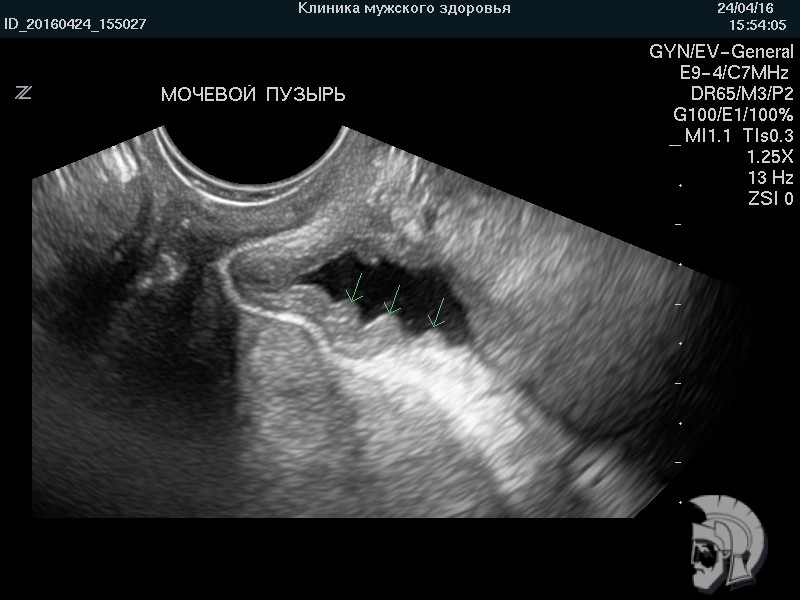

| Фото мочевого пузыря нетугого наполнения. Складки слизистой оболочки мочевого пузыря |